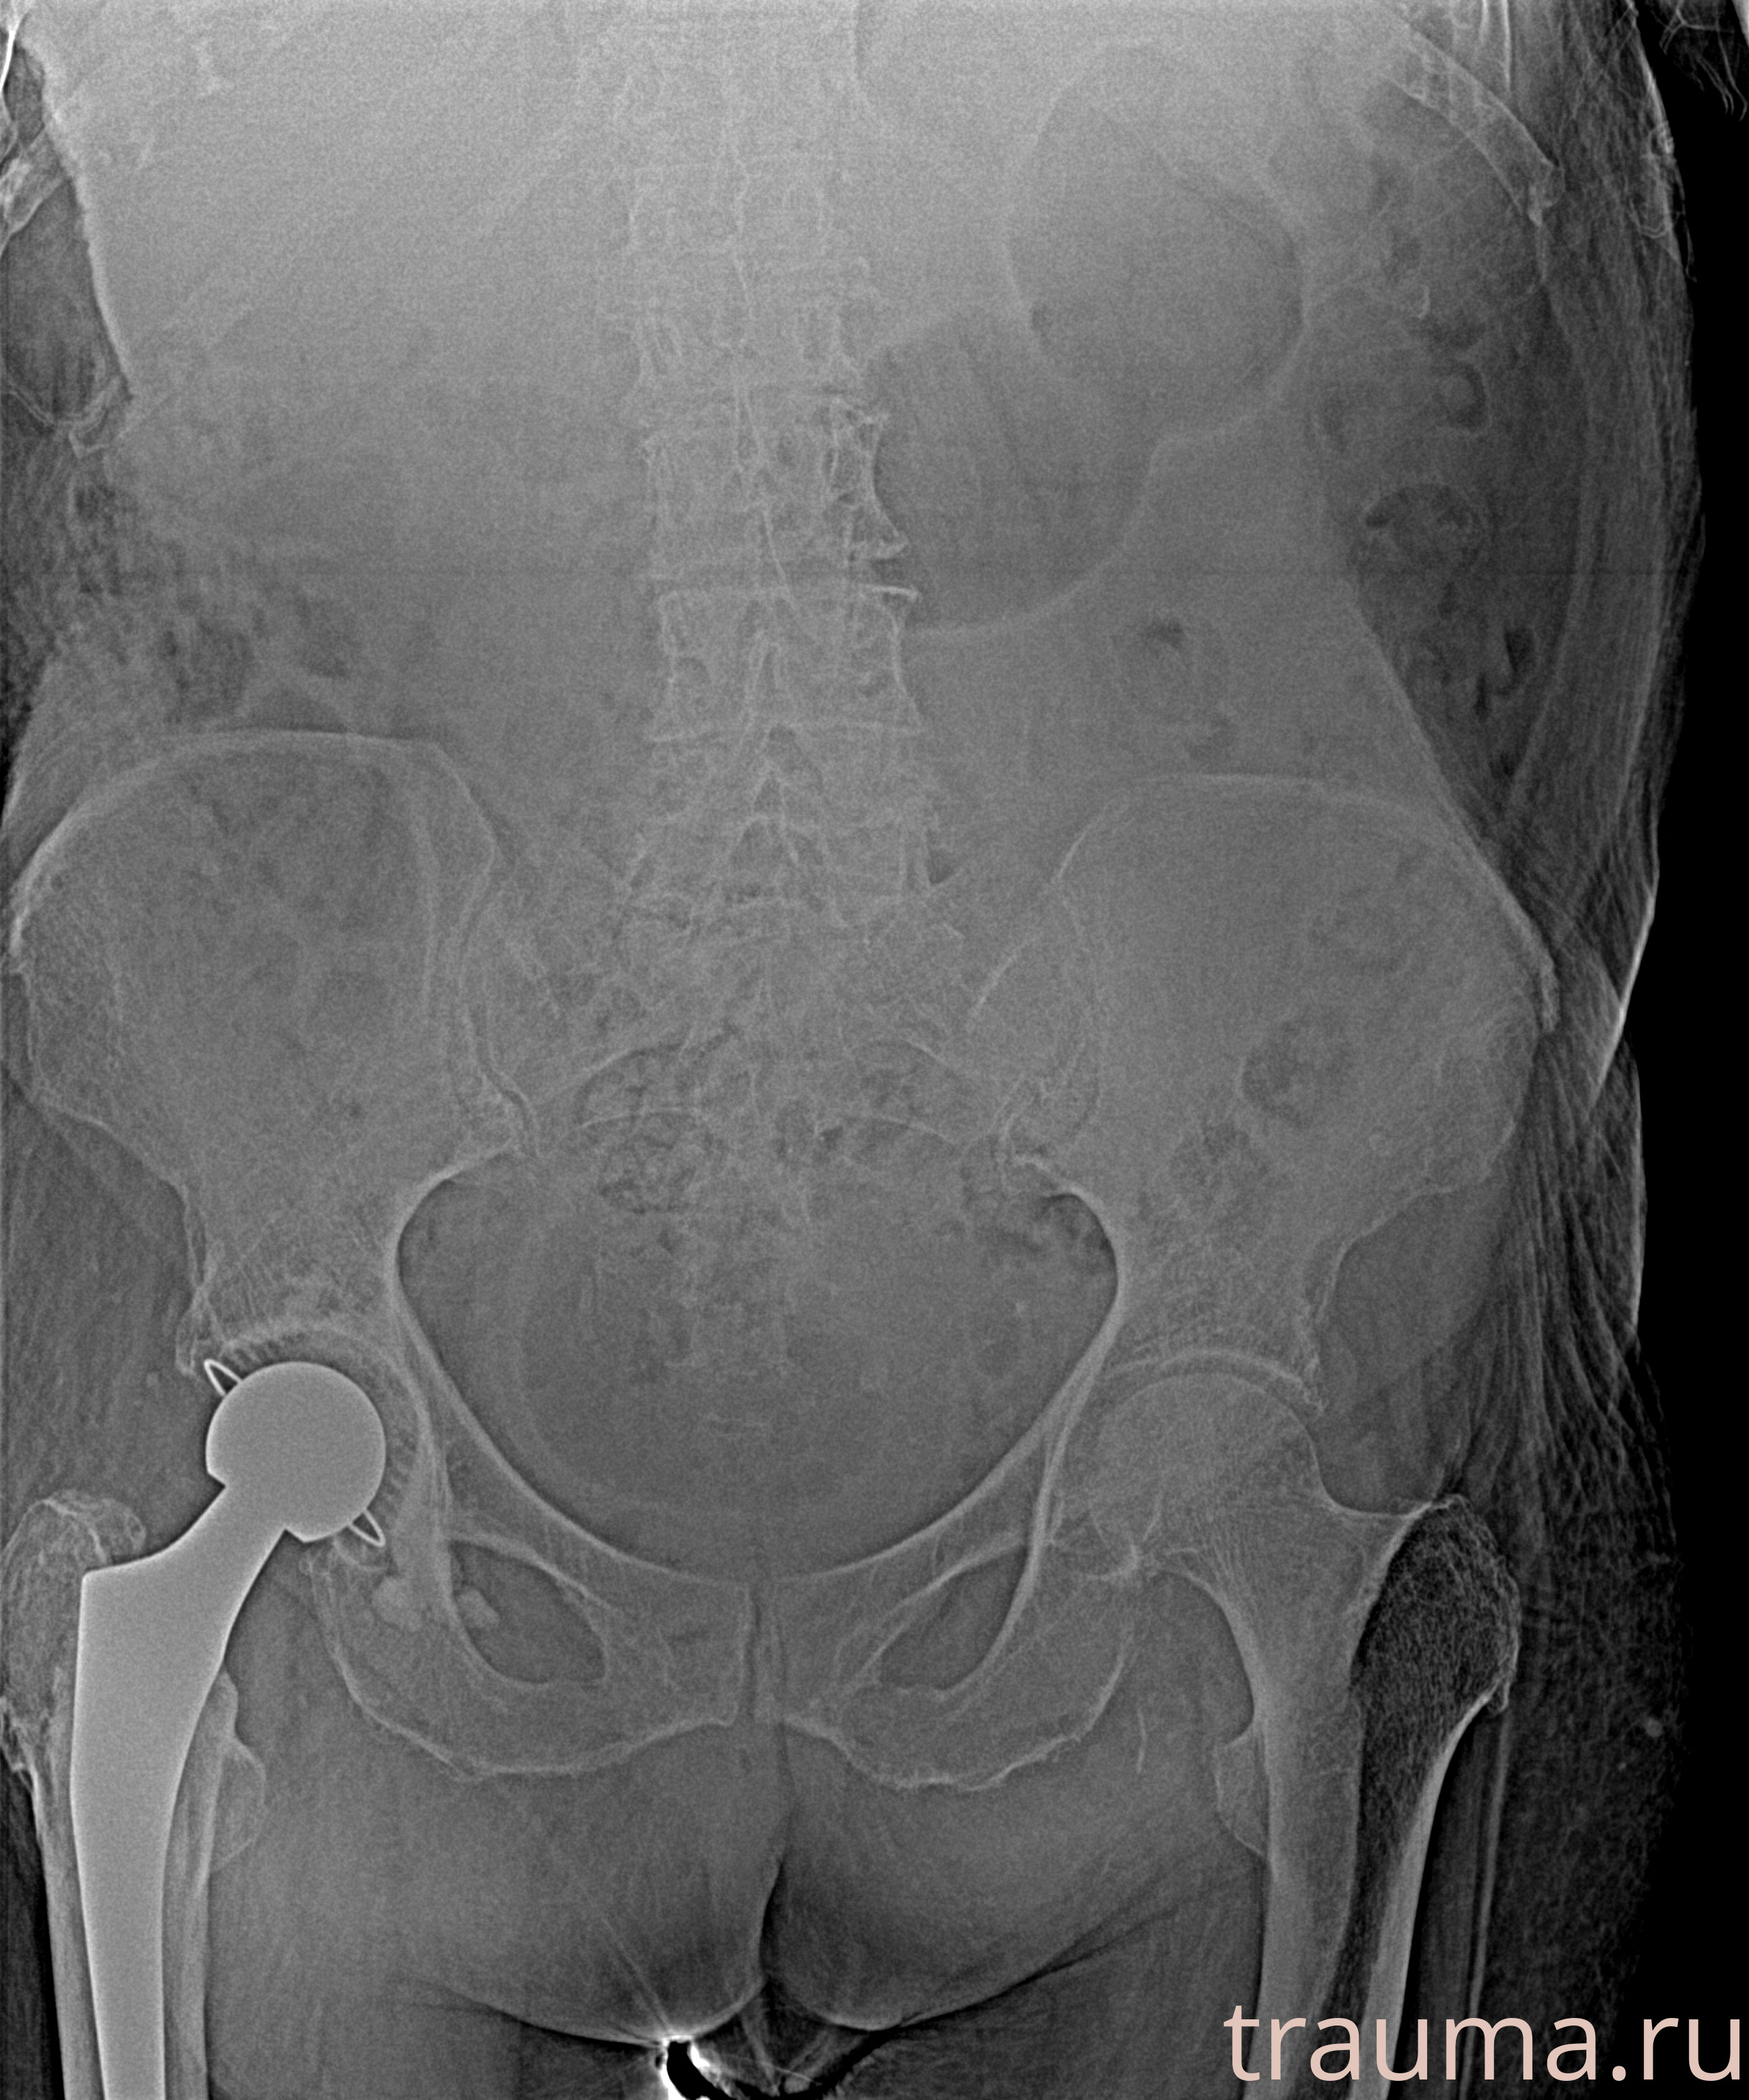

Первая помощь при переломе шейки бедра

Рентгенограммы

Рентген на дому: по вашему адресу приезжает врач-рентгенолог, травматолог-ортопед с мобильным рентгеновским аппаратом, проводит диагностику травмы или заболевания, делает необходимые рентгенограммы, дает рекомендации по дальнейшему лечению. Получить качественные снимки в домашних условиях возможно благодаря уникальной методике, разработанной МосРентген Центром для института  Склифосовского